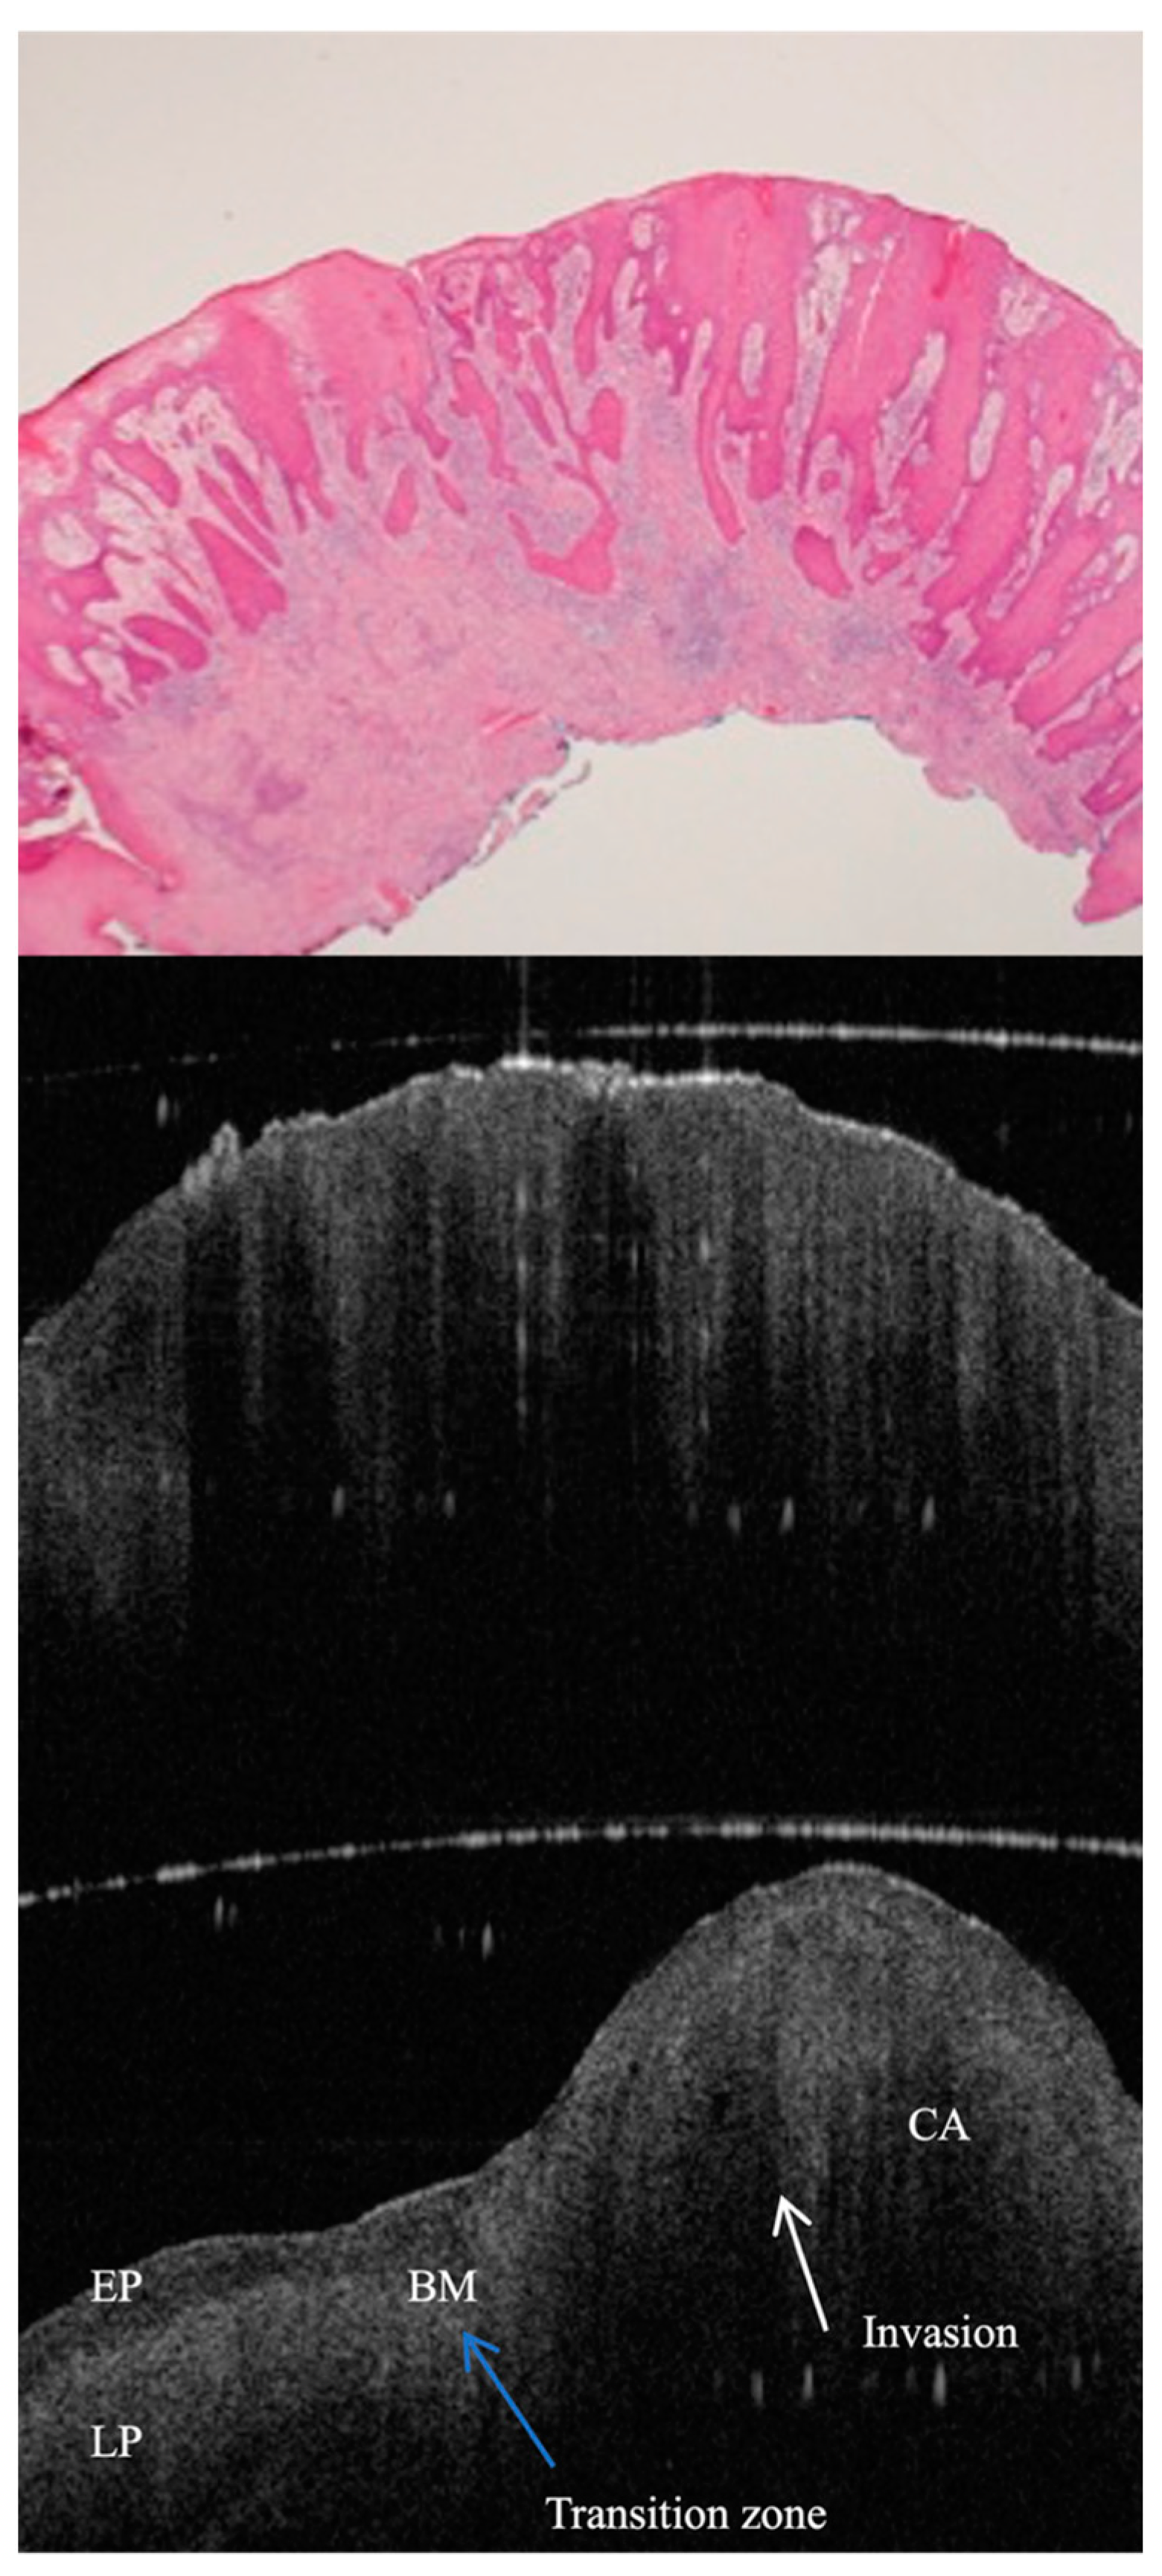

- Tsai, M.T.; Lee, H.C.; Lee, C.K.; Yu, C.H.; Chen, H.M.; Chiang, C.P.; Chang, C.C.; Wang, Y.M.; Yang, C.C. Effective indicators for diagnosis of oral cancer using optical coherence tomography. Opt. Express. 2008, 16, 15847–15862. [Google Scholar]

- Lee, C.K.; Chi, T.T.; Wu, C.T.; Tsai, M.T.; Chaing, C.P.; Yang, C.C. Diagnosis of oral precancer with optical coherence tomography. Biomed. Opt. Express. 2012, 3, 1632–1646. [Google Scholar] [CrossRef] [PubMed]